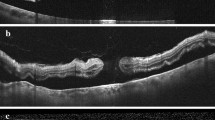

MHRD: Mean baseline best corrected visual acuity (BCVA) was 1.60 logMAR. All cases underwent pars plana vitrectomy (PPV). Mean post-operative BCVA was 1.49 logMAR (p = 0.674). The macular hole was closed in 5/20 (25%) cases, open/flat in 10/20 (50%) cases and open/elevated in 4/20 cases (20%). MRS: Mean baseline BCVA was 0.87 logMAR in the surgical group and 0.45 logMAR in the conservatively managed group (p = 0.002). All eyes that had surgical intervention underwent PPV. Mean post-operative BCVA was 0.68 logMAR (p = 0.183). Anatomical outcomes demonstrated a persistent MRS in 2/27 (7.4%) cases, partial resolution in 7/27 (25.9%) cases and complete resolution in 16/27 (59.2%) cases.